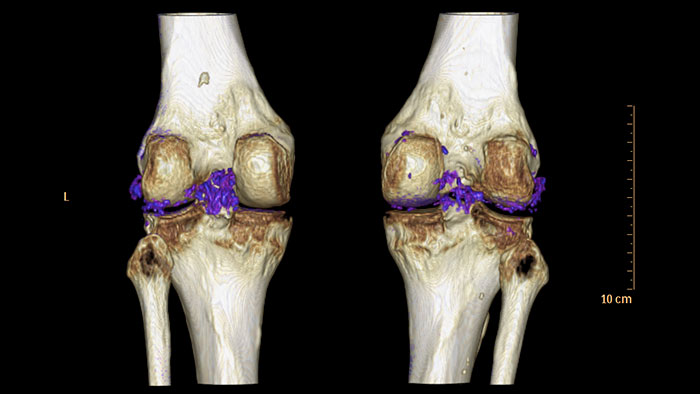

Visualize data from dual-energy acquisition

CT Dual Energy Viewer provides a set of tools for registration, quantification, and visualization of dual-energy image data acquired from the Philips iCT scanner’s sequential dual-energy acquisition.